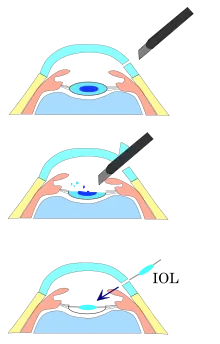

Lens insertion

As with other cataract removal procedures, an intraocular lens implant (IOL) is usually placed into the remaining lens capsule ("in-the-bag" implantation). For implanting a rigid poly(methyl methacrylate) (PMMA) IOL, the incision has to be enlarged, so this is not usually done. For implanting a foldable IOL, the incision does not have to be enlarged. The foldable IOL, made of silicone or acrylic of appropriate power, is folded either using a holder/folder, or a proprietary insertion device provided along with the IOL. Because a smaller incision is sufficient, no stitches should be needed, and recovery time is usually shorter when using a foldable IOL.[19][20]

Aligning the IOL in the correct axis to counteract astigmatism is necessary for a toric IOL.[21] Sometimes, a ciliary sulcus implantation may be required because of posterior capsular tears or because of zonular dialysis.